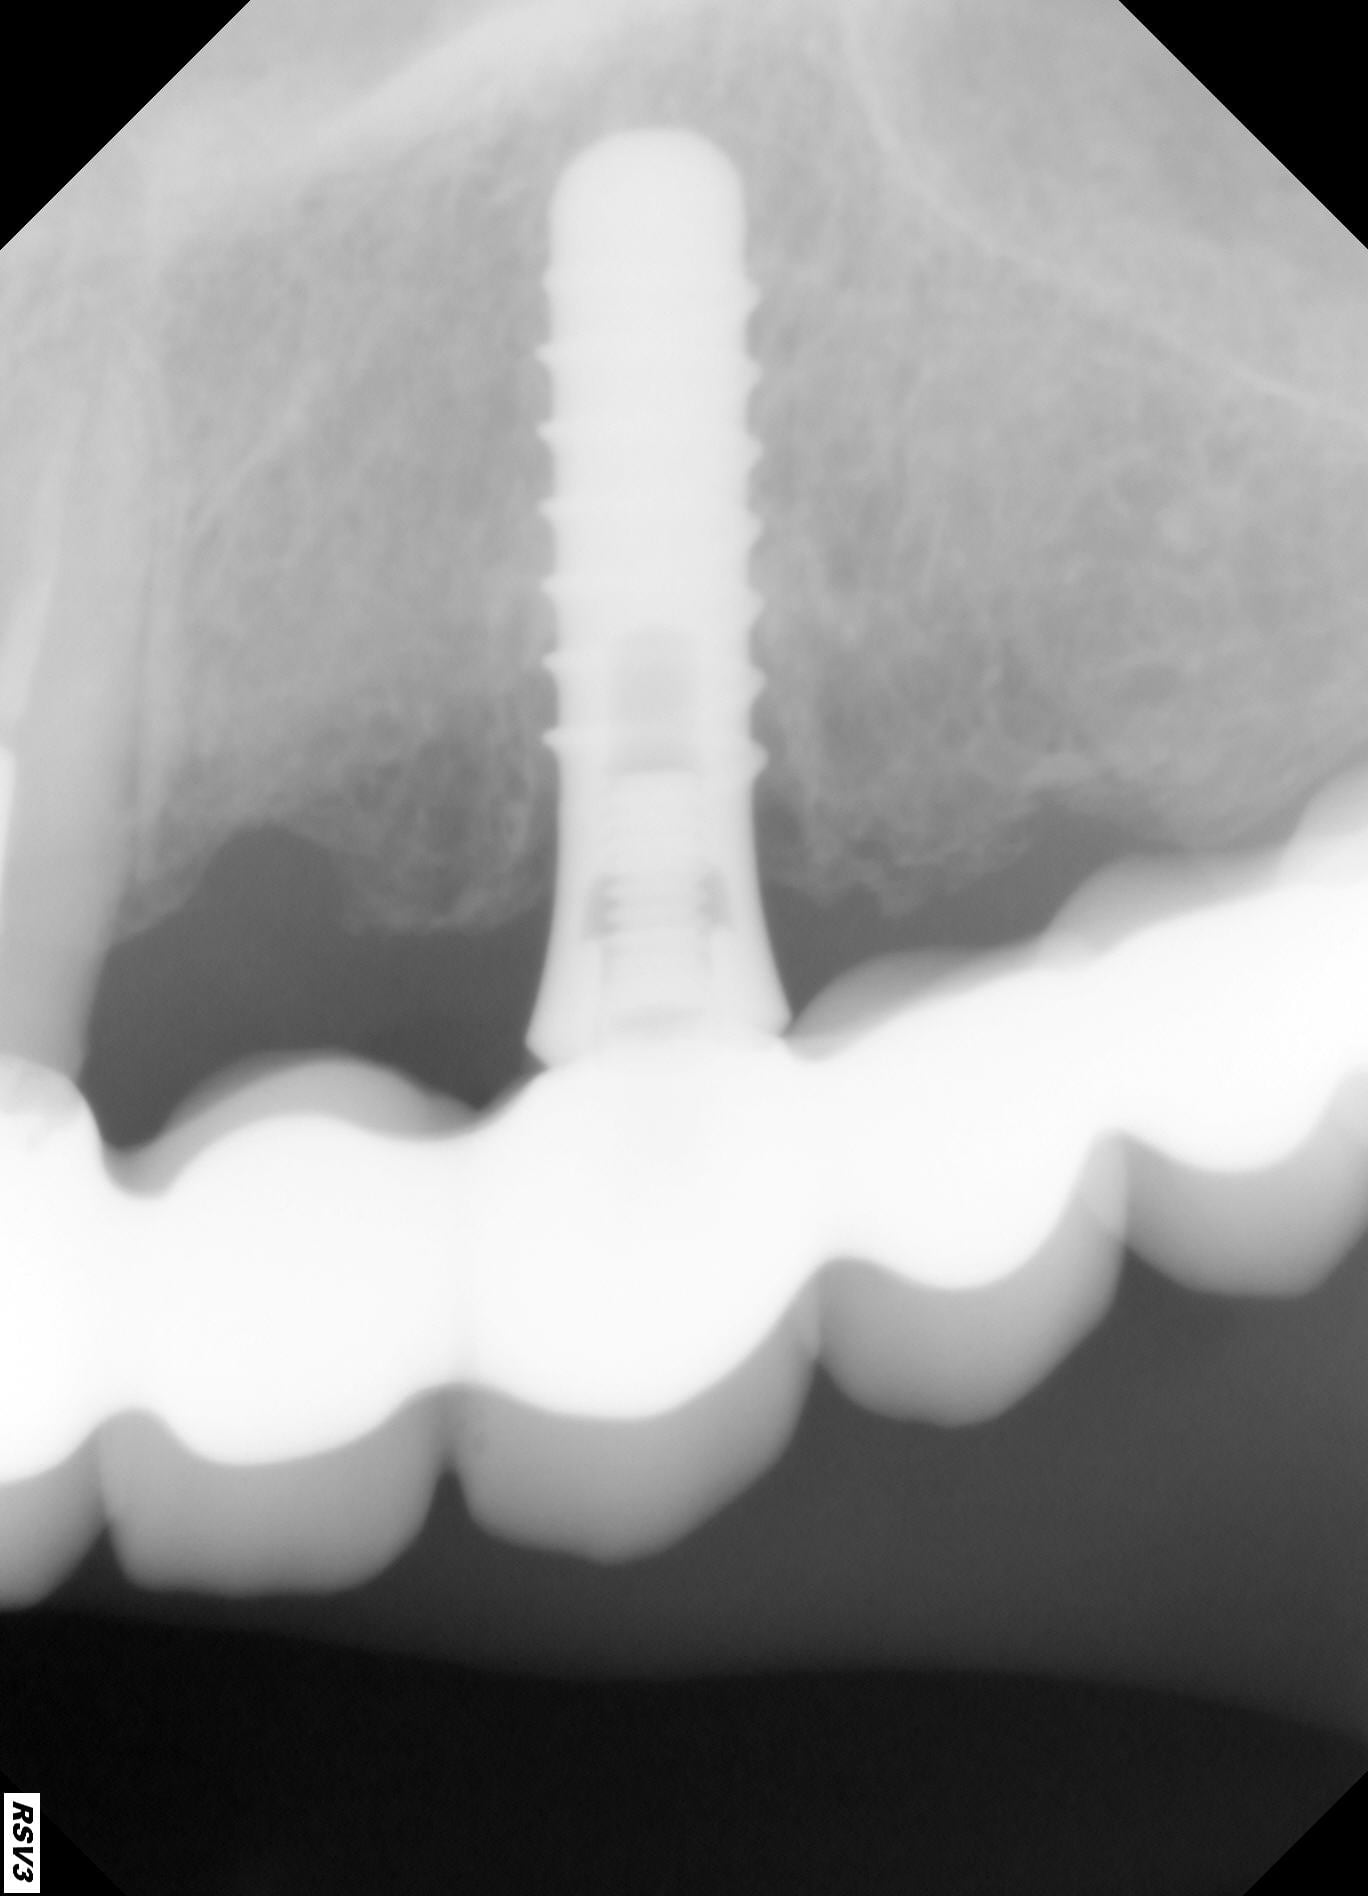

pouvez vous identifier cet implant svp,

je pense à du Straumann tissu level, mais lequel RN, NN ou WN?

Straumann tissue level oui, plateforme…..c’est toi qui peut dire en mesurant avec ton logiciel….

Quasi-certain qu'il s'agit d'un RN.